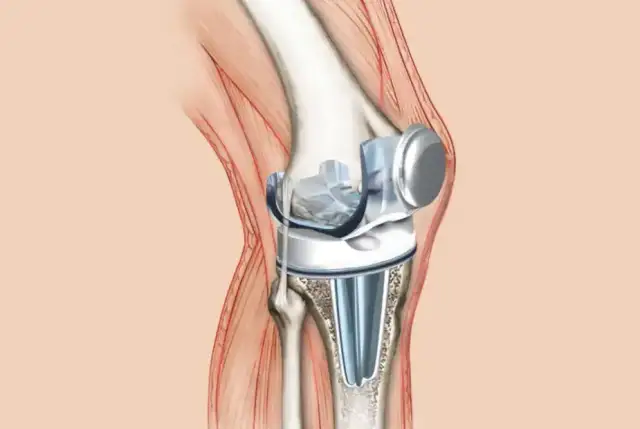

Rehabilitacja po endoprotezie kolana: Kluczowe etapy i ćwiczenia

Zastanawiasz się, jaka rehabilitacja po endoprotezie kolana jest najbardziej efektywna? Poznaj kluczowe etapy i ćwiczenia, które przyspieszą Twój powrót do zdrowia.